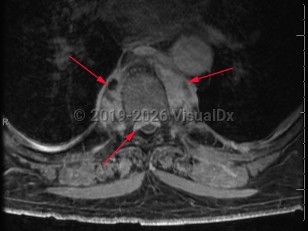

Paraspinal abscess

Paraspinal abscess is a collection of pus located around the spinal cord. This is usually seen as a complication of vertebral osteomyelitis and discitis (diskitis) but may be related to hematogenous seeding during bloodstream infection. Epidural catheters and injections may lead to direct inoculation of the epidural space. Frequently, the location of the abscess is in the epidural space.